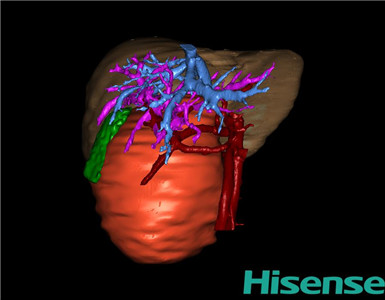

术前三维重建及手术方案设计:

将0.625mm双源薄层CT资料的静脉期和动脉期Dicom格式文件导入海信CAS系统。

通过调节窗宽窗位调整CT序号,对肿瘤、肝实质,胆囊,下腔静脉,肿瘤,肝动脉、门静脉及肝静脉等进行三维重建;系统自动计算肿瘤体积和肝脏体积。

模拟手术操作,自动计算切除肿瘤体积。肝脏体积为459.7ml,肿瘤体积为363.7ml,肿瘤体积为肝脏体积的79.12%,通过比对3-岁正常肝脏体积为248.41±85.99ml,通过术前模拟手术,精准判断切除后剩余肝脏体积能耐受,避免肝衰竭发生。

术前三维重建:

重建图片